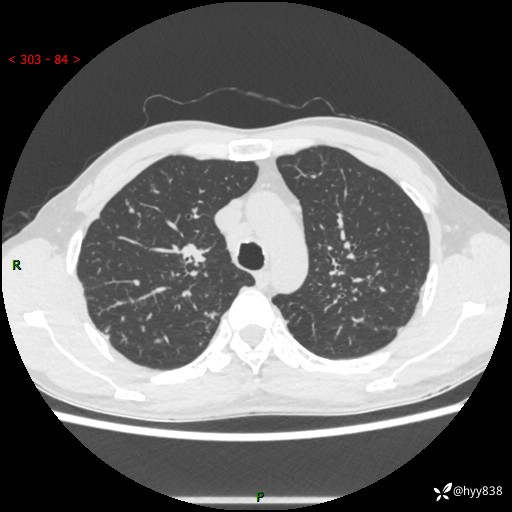

中年男性,咳嗽咳痰1月余。细看:肺、肺门、气管,貌似都有问题---(有结果)

现病史:患者于1个月前受凉后出现间断性咳嗽,伴白色泡沫样痰,无发热寒战、咯血、胸痛胸闷、恶心呕吐、呼吸困难等特殊不适,起初未予特殊处理,后患者就诊当地中医医院,查胸部CT提示支气管炎并双肺感染性病变,经抗感染(哌拉西林舒巴坦),止咳化痰(溴己新、三拗片)等治疗后,患者自诉咳嗽咳痰症状较前缓解,未诉发热等其他特殊不适,近期复查CT提示“肺部感染灶未见消退,双侧肺门增大,双肺散在小结节”,今为求进一步诊治,前来我院就诊,门诊以“肺部感染”收住入院。 患者自起病来精神、食欲、睡眠尚可,大小便正常,体力、体重无明显变化。

胸部CT平扫+增强(两期)